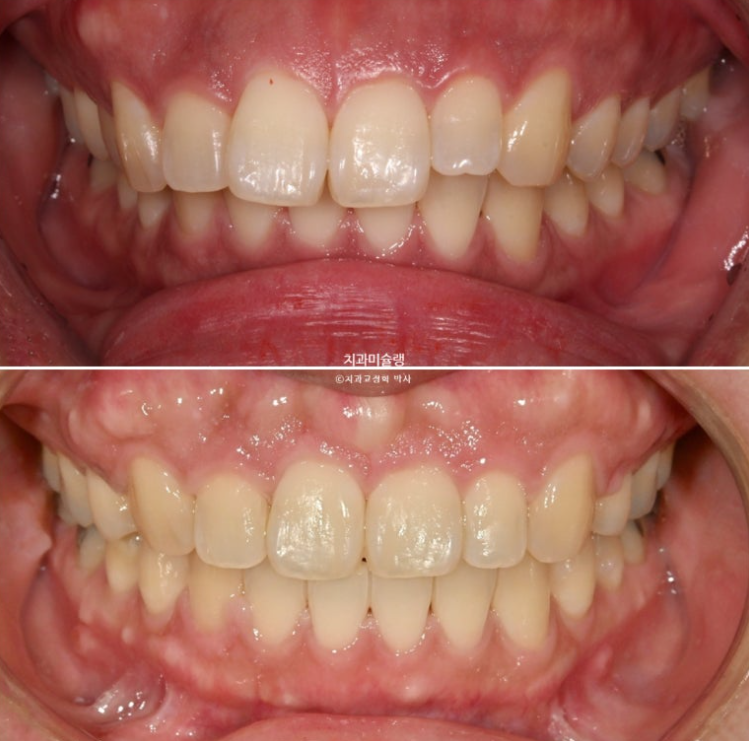

The midline and deep overbite have improved.

A stable, secure occlusal relationship is a given.

Let’s compare the before and after.

The total treatment period was 3 years. If the patient had visited once a month, it would likely have taken about 2 years and 3 months.

If you compare the before-and-after photos, you can see that the previously flat gum area above the front teeth has become uneven.

It is easy to misunderstand this as bone growing and protruding more than before, but in fact, the protruding part is the original position of the bone from before treatment, when the gums were protruding.

When the front teeth are successfully moved backward, including the roots, the gum bone covering the tooth roots also naturally resorbs and moves backward together with the roots. This is the process by which gum protrusion is resolved.

However, some areas of gum bone stubbornly remain in their original position and do not resorb.

As a result, these areas can look relatively protruded compared with the surrounding area after treatment, and this is the reason why the gums sometimes look uneven after extraction orthodontics.

There is no need to worry too much. Over time, most of it naturally becomes flatter through bone remodeling.